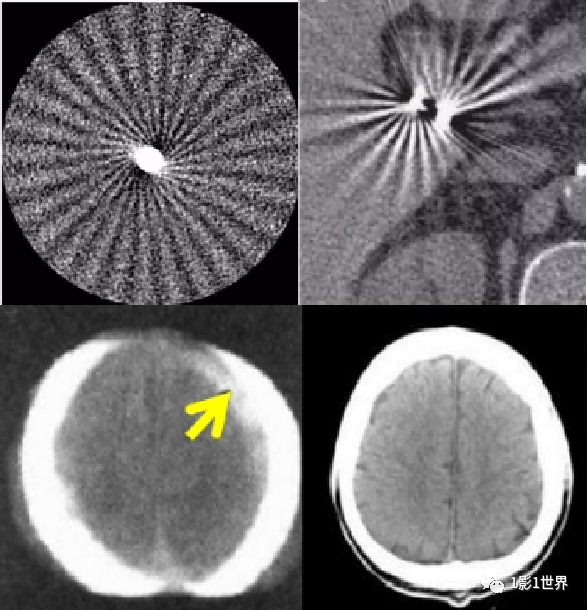

常见的有环状伪影、锥形伪影、带状伪影、射束硬化(放射状)伪影、部分容积伪影、条纹状、弧形、混杂伪影等等。

就伪影形成的原因,有设备本身因素,有扫描条件设置因素,有患者因素。正面,展示几种临床上常见的伪影,并分析其形成的原理,克服的办法。规范预热;定期空气校准;维护和保养;检测硬件故障,并更换。也叫条纹状伪影,表现为图像上低密直线,无规律出现。插值算法是导致这类伪影的主要原因。伪影的面积比,要随螺距的增大而增大。致密物体之间的条纹状低密度影;如头部后颅窝亨氏暗区,就是典型的更化束伪影。密度相差较大的物体之间的条带状高低密度影;如胃内气体较多时,肝胃之间的伪影。薄层扫描,厚层重建;改变体位